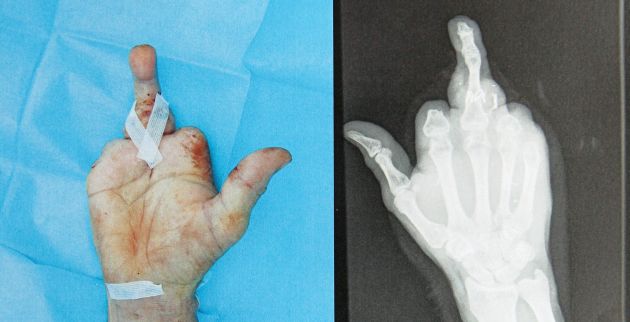

Επανάσταση στον τομέα των μεταμοσχεύσεων έκαναν Ισπανοί γιατροί, οι οποίοι κατάφεραν να προσφέρουν καλύτερη ποιότητα ζωής σε ασθενή που έχασε τα τέσσερα δάχτυλα του δεξιού του χεριού. Οι γιατροί προχώρησαν σε μερική αποκατάσταση μεταμοσχεύοντας στη θέση του μέσου δαχτύλου δάχτυλο από το πόδι του ασθενούς.

Ο 57χρονος Χουάν Κάρλος Γκοϊριένα δεκαπέντε ημέρες μετά την επέμβαση που έγινε στο Πανεπιστημιακό Νοσοκομείο De Cruces, στην πόλη Μπαρακάλδο, εμφανίστηκε δημόσια δηλώνοντας πως έχει αίσθηση του δαχτύλου του, σαν να προϋπήρχε στο χέρι του. Οσο για τους χειρουργούς του, μίλησαν για επιτυχημένη επέμβαση.

Ο Γκοϊριένα έχασε τα τέσσερα δάχτυλά του πριν από δέκα μήνες, όταν ενώ χειριζόταν τη μηχανή του γκαζόν, πιάστηκε το χέρι του και είδε τα τέσσερα δάχτυλά του να πέφτουν στο έδαφος. Παρά τον αρχικό τρόμο και τον πόνο του, τοποθέτησε τα κομμένα δάχτυλα σε μπολ με παγάκια και μεταφέρθηκε με ελικόπτερο στο νοσοκομείο, όπου όμως οι γιατροί απέρριψαν το ενδεχόμενο της συρραφής των δαχτύλων, δεδομένης της φύσης των τραυμάτων. Αργότερα, κι αφού ο ασθενής είναι δεξιόχειρας, οι γιατροί αποφάσισαν να προχωρήσουν στην επαναστατική επέμβαση μεταμοσχεύοντας το δεύτερο δάχτυλο του ποδιού του στο χέρι, ώστε, να μπορεί να πιάνει αντικείμενα, εφόσον ο αντίχειρας δεν είχε κοπεί. Θεωρούν ότι μετά την αποθεραπεία ο Γκοϊριένα, θα εκτελεί βασικές δραστηριότητες, όπως να κρατά στυλό, να δένει τα κορδόνια των παπουτσιών του ή να ανοίγει μπουκάλια. Δεκαπέντε ημέρες μετά την επέμβαση ο ασθενής άρχισε ήδη διαδικασία αποκατάστασης της κινητικότητας του δαχτύλου του, μέσω φυσικοθεραπείας, ενώ θα συνεχίσει αργότερα με ασκήσεις.

Σε ό,τι αφορά τον ακρωτηριασμό του δαχτύλου του ποδιού, σε πέντε εβδομάδες θα είναι σε θέση να περπατήσει χωρίς πατερίτσες. Ο πλαστικός χειρουργός Χουάν Χοσέ Γκαρθία, επικεφαλής της ιατρικής ομάδας που συμμετείχε στην πρωτοποριακή επέμβαση, η οποία διήρκεσε δέκα ώρες, μίλησε για τις δυσκολίες που αντιμετώπισε και αφορούσαν κυρίως την αναδόμηση ιστών και την ανάκτηση της λειτουργικότητας του δαχτύλου, κάτι που έχει να κάνει με την αποκατάσταση αρτηριών, φλεβών, τενόντων, νεύρων και οστών.